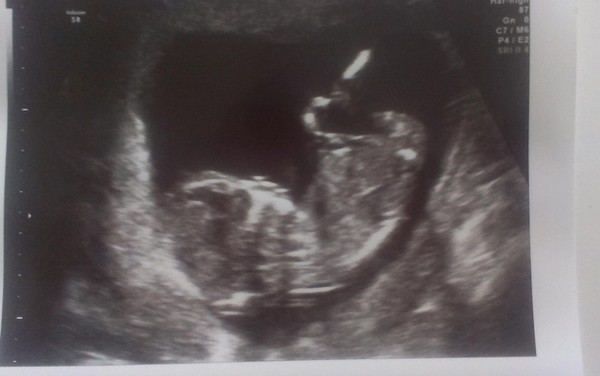

Hello ladies! Haven't been on for a while because I found the wait for 12-week scan quite stressful as the hospital left it very late... lovely to see the scans, good results and newbies though Flowers

Finally had my scan this afternoon, dates moved up so I'm 13+5 and pic attached. Baby didn't really want to cooperate with scan, mostly lay with its back to the probe and just wiggled a bit, so a tentative nuchal measurement of 2.4mm which I'm reasonably happy about. Just about ready to believe that this might actually happen! Smile

Lovely pic monk!

Cute scan pic monkerina!